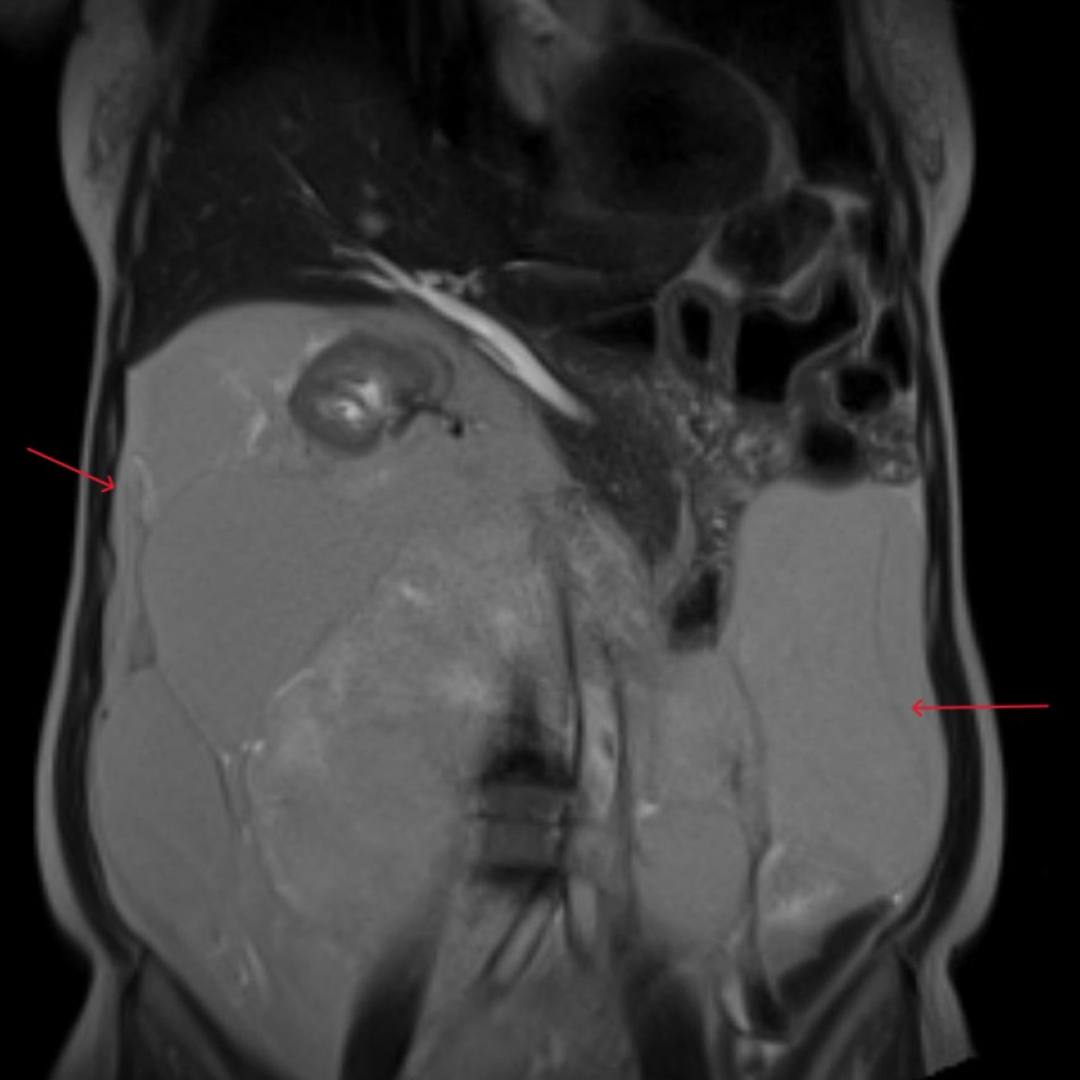

С целью оценки образования, а также уточнения расположения и взаимоотношения с органами брюшной полости проведено МРТ органов брюшной полости с внутривенным контрастированием.

При МРТ было выявлено жиросодержащее внеорганное объемное образование больших размеров с множественными неравномерными накапливающими контрастный препарат перегородками, занимающее большую часть брюшной полости с признаками смещения прилежащих внутренних органов.

Учитывая особенности структуры образования, распространенность и расположение, находка расценена как липосаркома (злокачественная опухоль жировой ткани).